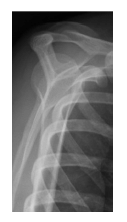

Analise a imagem ao lado:

Qual incidência radiográfica é mostrada nesta imagem?